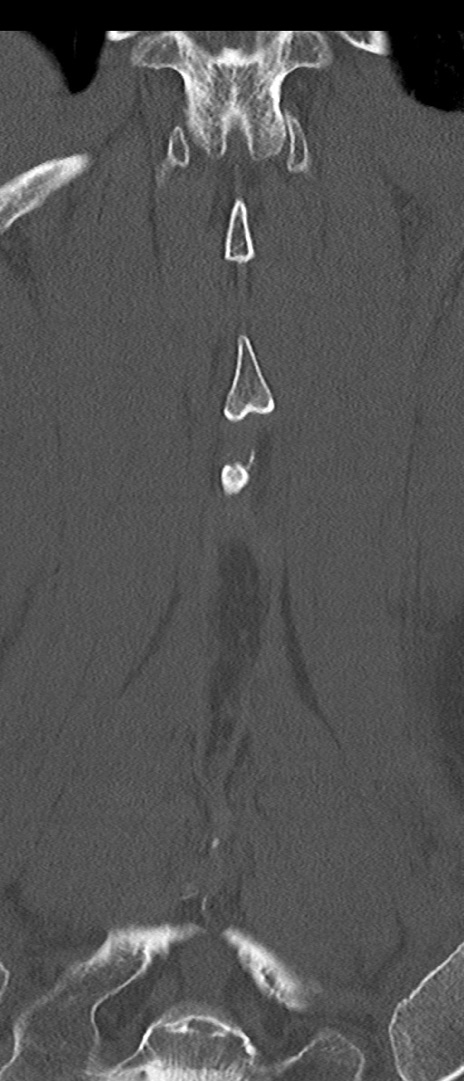

【整形】TIPS症例4 腰椎CT(冠状断像)

腰椎CT

矢状断像